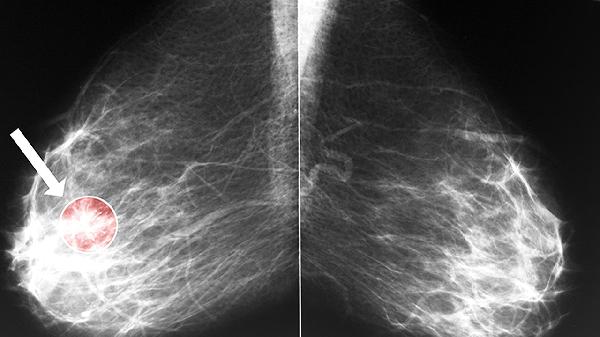

支氣管癌早期癥狀隱匿,典型表現(xiàn)包括持續(xù)性咳嗽、痰中帶血、胸痛、呼吸困難和體重下降,需及時(shí)就醫(yī)排查。

刺激性干咳是支氣管癌最常見首發(fā)癥狀,多因腫瘤刺激支氣管黏膜或阻塞氣道引發(fā)。隨著病情進(jìn)展,咳嗽可能轉(zhuǎn)為持續(xù)性并伴金屬音,夜間加重。中醫(yī)認(rèn)為此屬肺失宣降、痰瘀互結(jié),可配合潤肺化痰中藥如川貝母、杏仁,同時(shí)需進(jìn)行胸部CT或支氣管鏡檢查明確診斷。

約50%患者出現(xiàn)痰中帶血絲或少量咯血,源于腫瘤表面血管破裂。中醫(yī)辨證多屬肺絡(luò)損傷,可用白及、三七粉止血。需警惕大量咯血可能,現(xiàn)代醫(yī)學(xué)可通過血管介入栓塞治療,同時(shí)需排除肺結(jié)核等疾病。